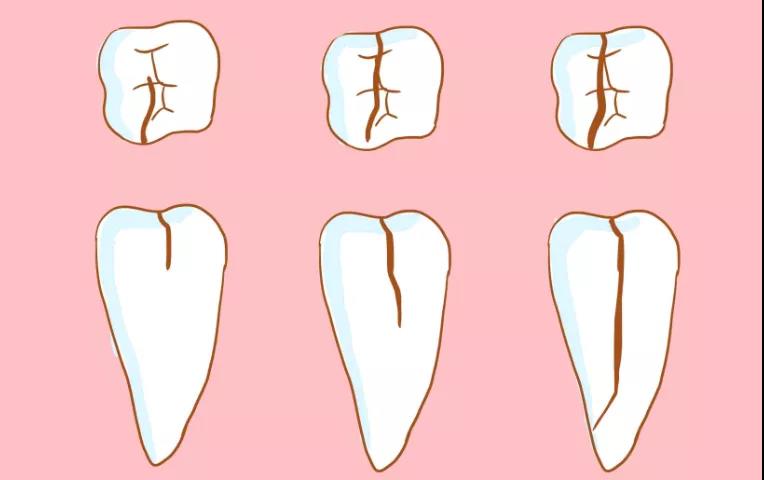

牙隐裂又称“不全牙裂”或“牙微裂”,是指牙冠表面出现非生理性的细小裂纹。

当牙齿因病理性磨损出现高陡牙尖时,吃东西会令牙尖压力增加,使窝沟底部的釉板向牙本质方向加深加宽,这就是隐裂纹的开始。

在力的继续作用下,裂纹逐渐向牙髓方向加深,从而形成了真正的牙齿隐裂。

病有轻重缓急,牙隐裂,也是一样。不同深度的裂纹,疼痛的感觉患病的严重性也不一样。

☛ 裂纹较浅:肉眼很难看到裂纹,偶尔吃过冷或过热的食物时,牙齿会产生短促又剧烈的疼痛。

☛ 裂纹较深:牙齿会经常性地疼痛,咬合不适或有轻度的叩痛感。

☛ 裂纹深达牙本质:牙齿会出现慢性牙髓炎症状,冷热刺激患牙时,产生剧痛,咀嚼过程中可能会疼痛难忍。